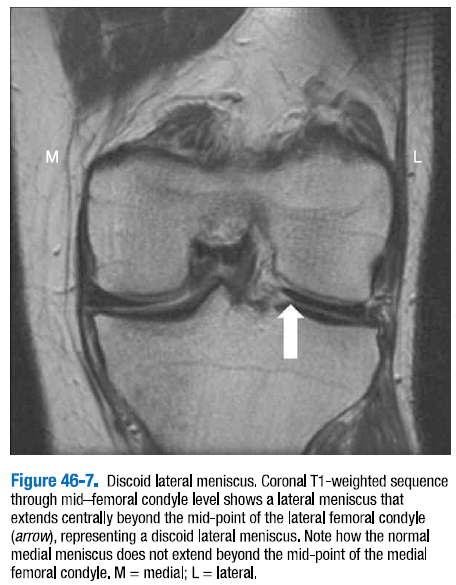

원반형 반월판(Discoid meniscus)이 인구의 3% 정도로 발생하는 흔한 변이에 해당하는데, 반월판의 형태학적인 거대화로 나타난다. (그림 46-7) 환자는 대개 무릎을 신전하고 굴곡할 때 염발음을 나타낸다. 이는 관상면 상에서 최적으로 진단되고 시상면 상에서는 그렇지 않은데, 기술상의 다양함이 나타날 수 있다. 대퇴외과의 중간 레벨을 관통한 관상면 MRI 영상에서 대퇴외과의 중간 포인트 아래로 가운데 부위로 이어지는 반월판이 원반형 반월판(discoid meniscus)으로 불린다.

△ 그림 46-7. 외측 원반형 반월판

중간 대퇴외과 레벨을 통과하는 관상면 T1 강조 시퀀스는 외측 원반형 반월판으로 나타나는 외측 반월판이 외측 대퇴외과의 중간 포인트 아래 가운데 부위로 연장됨을 보여준다. (화살표) 정상적인 내측 반월판은 내측 대퇴내과로 이어짐은 보이지 않는다. M = 내측, L = 외측